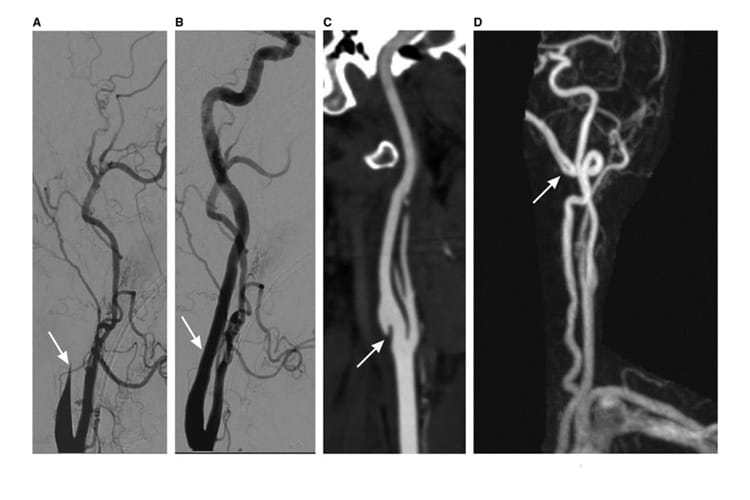

- Cervical artery dissection (CAD) is an important cause of stroke and stroke-related disability in young adults.

- CAD (either carotid or vertebral artery) can occur without major trauma.

- This scientific statement provides an overview of cervical artery dissection with current data presented and suggestions on the diagnostic evaluation, treatment approaches and clinical outcomes.